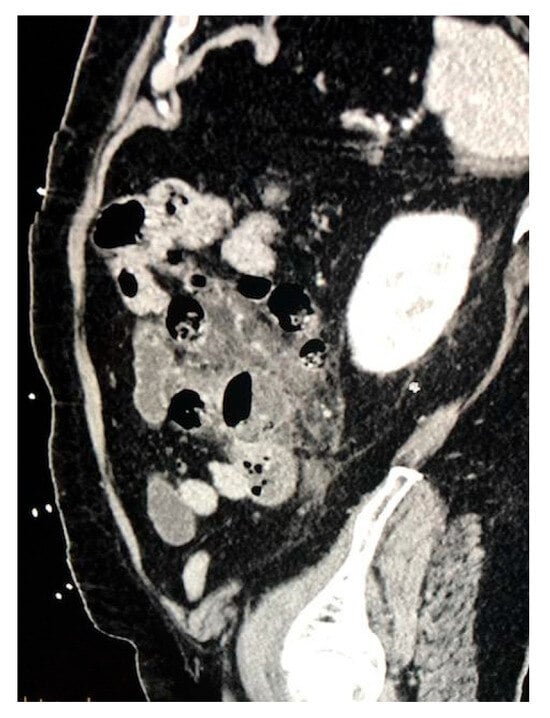

2. Case Presentation